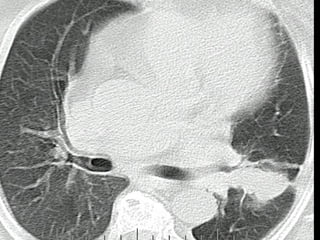

Posteroanterior chest radiograph shows an elevated left hemidiaphragm, suggestive of phrenic nerve involvement by the mass.  Lateral chest radiograph shows extension of the mass to the anterior chest wall  (arrow) .  Computed tomography suggests both pericardial and chest wall involvement  (arrows) . At thoracotomy, the chest wall, phrenic nerve, and pericardium was found to be involved. All were resected  en bloc  with the tumor.

Posteroanterior chest radiographshows an elevated left hemidiaphragm, suggestive of phrenic nerve involvement by the mass. Lateral chest radiograph shows extension of the mass to the anterior chest wall (arrow) . Computed tomography suggests both pericardial and chest wall involvement (arrows) . At thoracotomy, the chest wall, phrenic nerve, and pericardium was found to be involved. All were resected en bloc with the tumor.